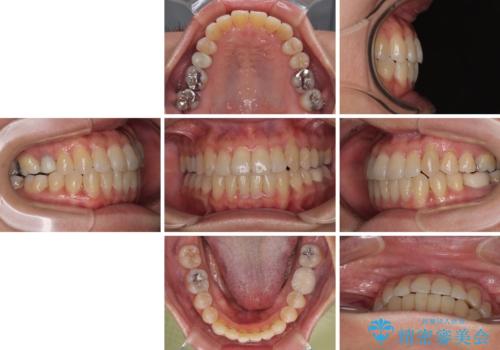

受け口と八重歯を改善 インビザライン矯正治療

受け口傾向のインビザライン矯正は比較的治療を行いやすいため、きれいに仕上げることができました。舌の突出癖が顕著であったため、改善のためのトレーニングをしっかりと行っていただきました。

受け口傾向の骨格であり、前歯はクロスバイトまたは切端咬合となっており、下顎を中心に歯列全体の後方移動を行い、IPR(歯と歯の間を削る)によってデコボコが解消するように設計し、インビザラインにより治療を行うこととしました。